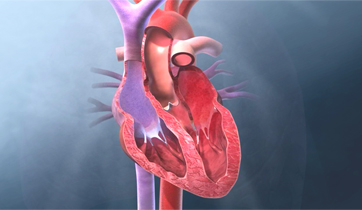

Diastolic Cardiac Insufficiency

Sanofi

ScienceProd, Paris

The Angiotensin - Aldosterone - Renin system is triggered by the thickening of the left ventricle and improper filling of the venticular chamber. This triggers the release of aldosterone, noradrenaline, and angiotensin II which binds to fibroblasts, releasing collagen and increasing myofibril rigidity.